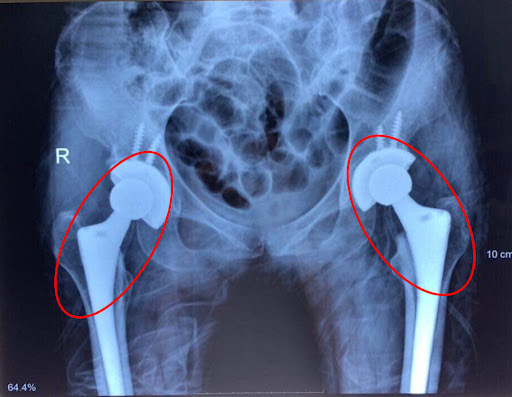

Phẫu thuật thay khớp háng

Mục đích của phương pháp phẫu thuật này là loại bỏ khớp háng bị tổn thương và thay thế bằng khớp nhân tạo, từ đó giúp bệnh nhân cải thiện khả năng hoạt động, đồng thời dễ dàng tái hòa nhập với cuộc sống thường ngày.

Thay khớp háng được phân loại thành hai dạng gồm:

- Thay một phần khớp háng: được chỉ định khi lớp sụn bị bào mòn và khớp chỉ bị tổn thương một phần.

- Thay khớp háng toàn phần: chủ yếu dành cho những trường hợp như sau:

- Người bệnh trên 60 tuổi

- Bệnh nhân có bệnh nền gây tổn thương khớp háng (viêm khớp dạng thấp, hoại tử xương…)

- Triệu chứng bệnh nghiêm trọng (các cơn đau kéo dài, ảnh hưởng đến giấc ngủ, gây khó khăn khi lên xuống cầu thang hoặc đứng lên từ tư thế ngồi…)